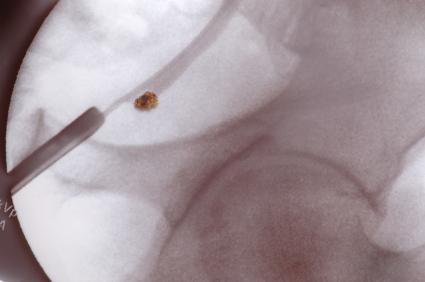

Дълго време бъбречно-каменната болест може да остане скрита – да няма никакви симптоми. Нефролитиазата трупа камъни в бъбречното легенче и неговите чашки. Когато се раздвижат по посока на уретера, пикочния канал и мехура, се явява болка. Урината става тъмна. Промяната на цвета се дължи на кръв в урината, която се отделя, когато острите ръбове на калциево-оксалатните камъни одраскат лигавицата.

При криза опитваме да тушираме болката. Пробваме различни аналгетици – аналгин, дексофен, аулин и др., и спазмолитици като но-шпа, бусколизин, антиспазмин, папаверин. Невинаги обаче се постига нужният ефект. Понякога се налага болнично лечение. Там обикновено се използват същите медикаменти, но венозно. Прилагат се и различни методи за изваждане или разбиване на камъните – апаратни методи за екстракция на камъка от уретрата, пикочния мехур и пикочопроводите. Нов и перспективен метод за разбиване на по-големите камъни е екстракорпоралната литотрипсия. Пациентът се поставя във вана с вода и със серия от ударни вълни камъкът се разрушава. Това лечение е подходящо, ако пикочопроводите не са блокирани, при големина на камъка до 2 сантиметра и ако, разбира се, няма инфекция.